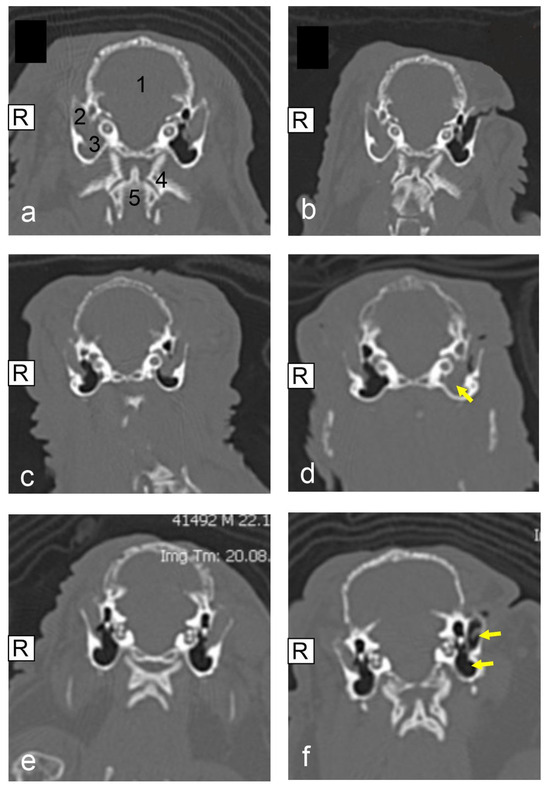

Evaluation of Lateral Ear Canal Ablation (LECA) as a Surgical Treatment Option for External Ear Canal Disease in Lop-Eared Pet Rabbits (Oryctolagus cuniculus)

by Anne Willems, Johannes Hetterich, Milena Thöle, Michael Pees, Michael Fehr and Maximilian Reuschel

Animals 2025, 15(8), 1142; https://doi.org/10.3390/ani15081142 - 16 Apr 2025

Viewed by 959

A soft tissue-filled external ear canal, sometimes also referred to as otitis externa in the veterinary literature, is a prevalent disease in pet rabbits, especially in lop-eared pet rabbits. The authors describe the clinical findings, diagnostic workup, therapy, and outcome of pet rabbits [...] Read more.

A soft tissue-filled external ear canal, sometimes also referred to as otitis externa in the veterinary literature, is a prevalent disease in pet rabbits, especially in lop-eared pet rabbits. The authors describe the clinical findings, diagnostic workup, therapy, and outcome of pet rabbits treated surgically for a lateral ear canal ablation (LECA). For the time period between 2015 and 2023, the medical records of two veterinary clinics were evaluated retrospectively. A total of 25 pet rabbits, diagnosed via computed tomography (CT) scans with a soft tissue-filled external ear canal and (if present) middle ear, were identified. All the pet rabbits were evaluated as lop-eared pet rabbits and all were treated surgically using the same surgical technique, LECA. In accordance with Richardson et al., we categorized the different ear filling levels by using the grading system that was established in 2019. The mean follow-up period was 19 days, and in one case complete wound healing was not reached within 131 days after surgery. A total of 7/25 of the pet rabbits were evaluated with wound healing issues. Of the cases, 18/25 did not develop any recurrent ear diseases. Loss to follow-up was observed in 5/25 of the cases and recurrent ear diseases were identified in 2/25 of the pet rabbits. Progression of the ear disease was detected in four cases. CT post-operative images were acquired for 14/25 of the pet rabbits. Based on this study, LECA can be considered a safe surgical method to treat soft tissue-filled external ear canals, especially in lop-eared pet rabbits. Nonetheless, thorough post-surgical management including wound control is critical for therapy success. Full article